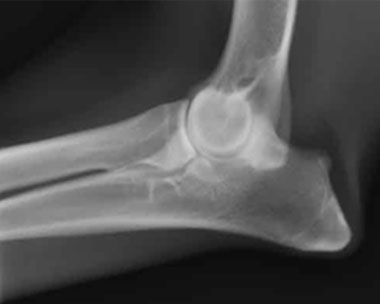

股関節と肘関節のX線検査とは - BVAシステム

BVAとは「British Veterinary Association(英国獣医師会)」の略で、この検査方式はイギリスで開発されたものです。スコアリングは左右両方の股関節に対して行われ、10項目に分けて評価し、それぞれの点数を合計して最終スコアを算出します。どれか1つの項目で4以上のスコアを示す場合、その犬は早期段階で退行性変化の兆候があるとされ、繁殖には不適と判断されます。犬種によってはスコアが高く出ることがあり、その場合は繁殖には向きません。合計スコアが100を超える場合もあります。

私たちの犬たちは長年にわたり、常に非常に低いスコアを維持しています。基本的には、オーストラリア国内のラブラドゥードルの平均値(合計12.75)を下回る犬を使用しています。オス犬に関しては、さらにスコアが低いことを絶対条件としており、基準を緩めるつもりはありません。

肘関節のスコアは0〜3の範囲で評価されます。私たちは、両肘のスコアが1を超える犬は絶対に繁殖に使用しません。0または1であれば繁殖に適しており、これまで当犬舎では肘関節形成不全の報告は一度もありません。